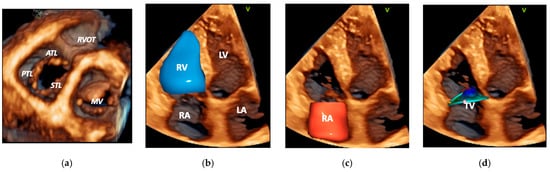

3.1. Echocardiography